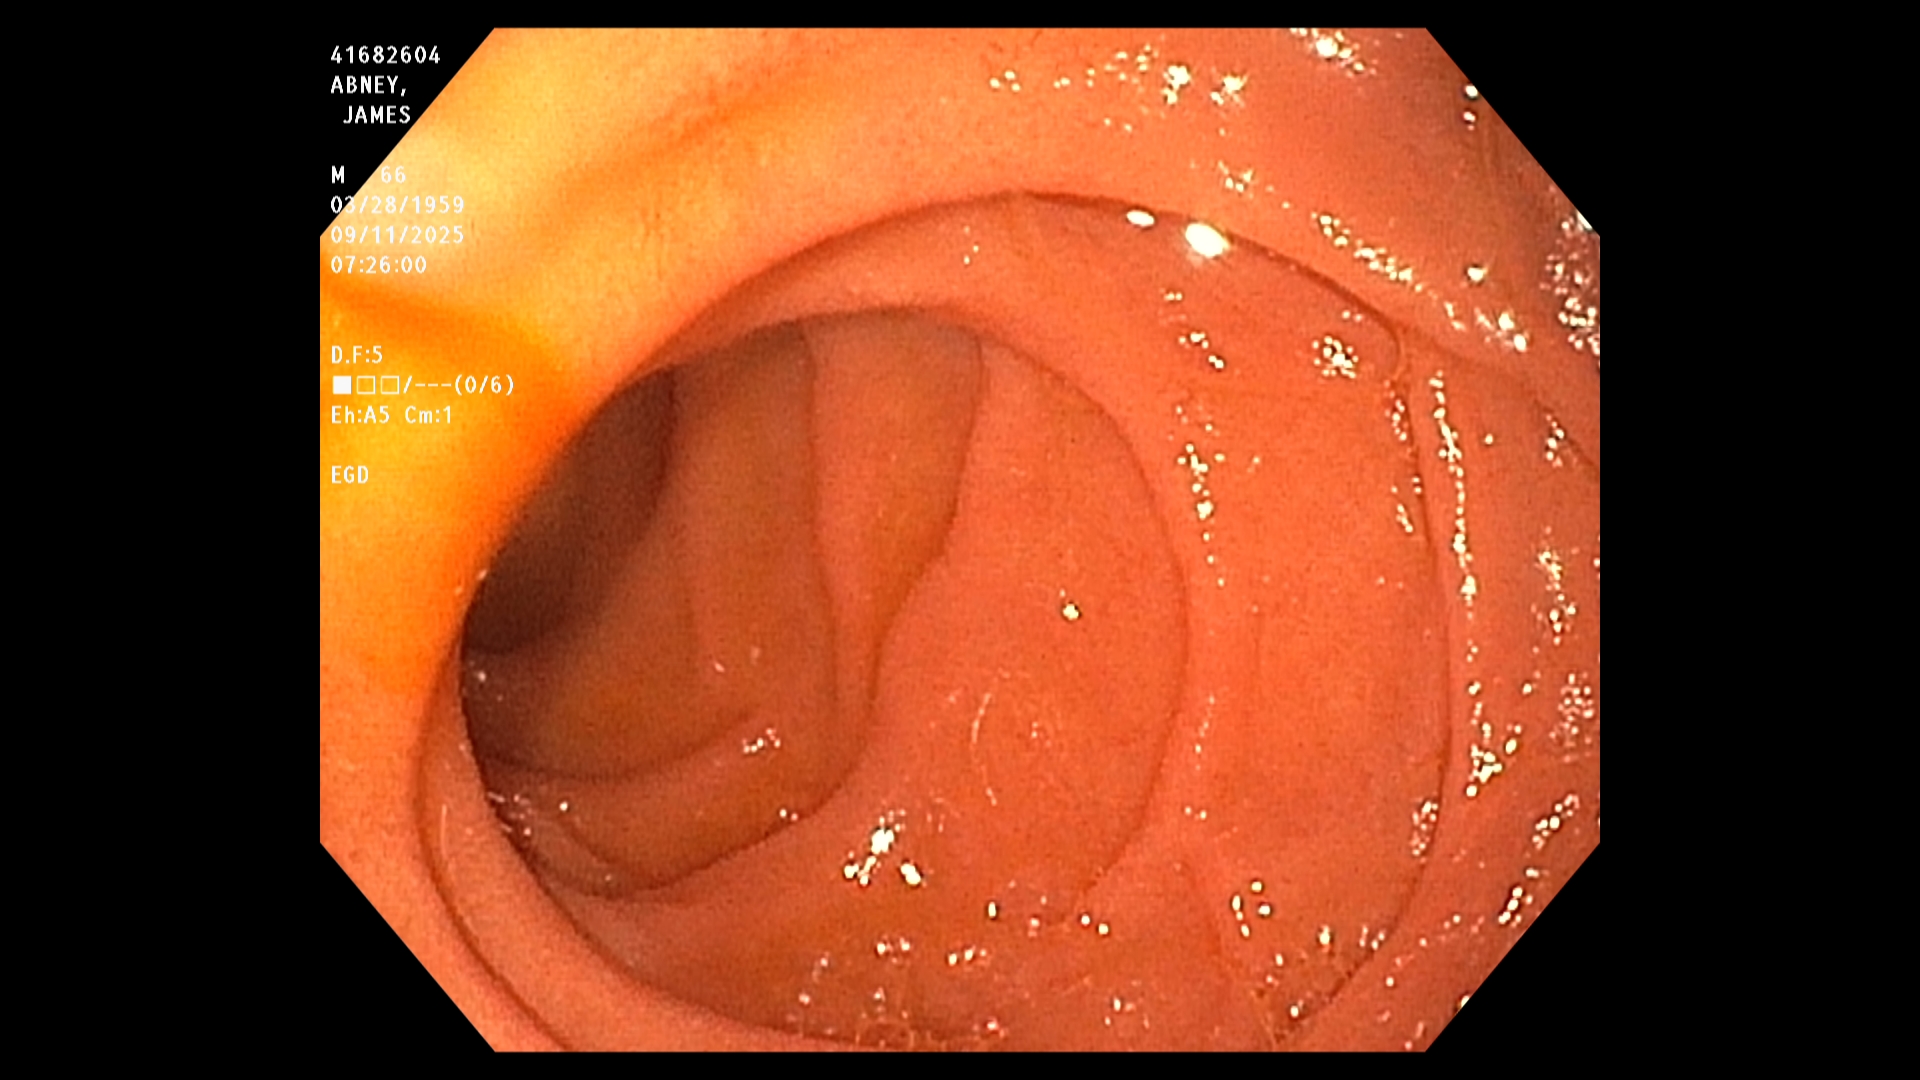

The endoscopist in this study generated a series of images showing the stomach, duodenum,

duodenal bulb, and esophagus, among others. The stomach was imaged first. The image is a

the endoscope. The endoscope was next passed into the duodenum, farther down the GI tract,

and then withdrawn while care was taken to observe mucosal detail.

The EGD results in this study were good. In particular, the endoscopist stated that all observed

structures appeared normal and that there was no evidence of any damage, including acid-

reflux damage.